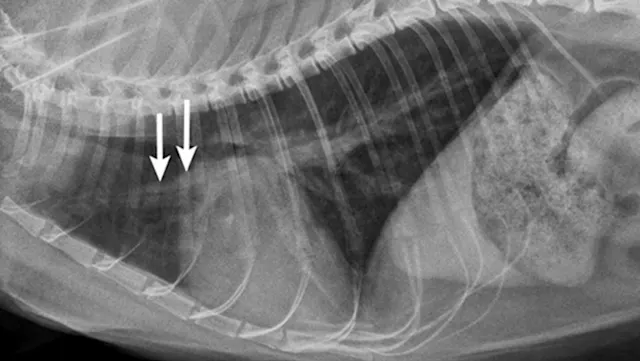

Primary cardiac disease that leads to CHF-related pulmonary edema commonly causes diffuse (perihilar in the dog) or variable (in the cat) interstitial and alveolar patterns. The vertebral heart score (VHS) is an objective method for evaluating the size of the cardiac silhouette (see Steps to Measure VHS). Certain cutoff values are used to determine whether acute respiratory distress is primarily pulmonary or cardiac in origin and to guide initial therapy for stabilization and planning for definitive cardiac or respiratory workup. A VHS <11.4 in the dog can help rule out mitral valve disease–related CHF as a cause for respiratory signs.3 Although an increased VHS can be associated with primary cardiac disease, it is not a specific characteristic in small-breed dogs because of their thoracic conformation.3 In the cat, a left lateral VHS ≤7.9 can reasonably rule out the presence of heart disease.4 Additional radiographic changes associated with primary cardiac disease include left atrial enlargement and pulmonary venous distension (Figures 1 and 2). Pleural effusion can be associated with CHF and primary pulmonary disease. A miliary pattern and/or solitary soft tissue densities in the lungs are indicative of primary pulmonary disease (Figure 3). Hyperinflation of the lung and distinct peribronchial markings are supportive of lower airway disease, although peribronchial markings can be found in the cat with CHF.

Right lateral thoracic radiograph of a dog that was presented with labored breathing and a moist cough. The patient had a history of a heart murmur, and the breathing pattern was synchronous with increased effort on inhalation. Thoracic auscultation revealed diffuse, soft moist crackles and a 4/6 left systolic heart murmur over the mitral region. Butorphanol and furosemide were administered and the patient was allowed to rest with supplemental oxygen before radiography. Radiographs showed a VHS of 12.5, significant left atrial enlargement (white arrows), and pulmonary venous distension (black arrows) consistent with left-sided heart failure. Mitral valve insufficiency caused by valvular endocardiosis was confirmed with echocardiography.